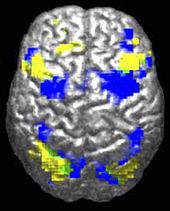

Research into causes has been hampered by the inability to identify biologically meaningful subgroups within the autistic population and by the traditional boundaries between the disciplines of psychiatry, psychology, neurology and pediatrics. Newer technologies such as fMRI and diffusion tensor imaging can help identify biologically relevant phenotypes (observable traits) that can be viewed on brain scans, to help further neurogenetic studies of autism; one example is lowered activity in the fusiform face area of the brain, which is associated with impaired perception of people versus objects. It has been proposed to classify autism using genetics as well as behaviour.

ASD-related patterns of low function and aberrant activation in the brain differ depending on whether the brain is doing social or nonsocial tasks. In autism there is evidence for reduced functional connectivity of the default network, a large-scale brain network involved in social and emotional processing, with intact connectivity of the task-positive network, used in sustained attention and goal-directed thinking. In people with autism the two networks are not negatively correlated in time, suggesting an imbalance in toggling between the two networks, possibly reflecting a disturbance of self-referential thought. A 2008 brain-imaging study found a specific pattern of signals in the cingulate cortex which differs in individuals with ASD.

The underconnectivity theory of autism hypothesizes that autism is marked by underfunctioning high-level neural connections and synchronization, along with an excess of low-level processes. Evidence for this theory has been found in functional neuroimaging studies on autistic individuals and by a brainwave study that suggested that adults with ASD have local overconnectivity in the cortex and weak functional connections between the frontal lobe and the rest of the cortex. Other evidence suggests the underconnectivity is mainly within each hemisphere of the cortex and that autism is a disorder of the association cortex.

From studies based on event-related potentials, transient changes to the brain's electrical activity in response to stimuli, there is considerable evidence for differences in autistic individuals with respect to attention, orientiation to auditory and visual stimuli, novelty detection, language and face processing, and information storage; several studies have found a preference for nonsocial stimuli. For example, magnetoencephalography studies have found evidence in autistic children of delayed responses in the brain's processing of auditory signals.